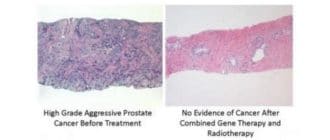

腫瘍細胞を攻撃する免疫系を引き起こす前立腺癌の遺伝子治療の長期間の臨床試験は、それが効果的かつ安全であることを示唆している、と研究者らは言う。 前立腺癌では、他の多くの癌と同様に、腫瘍細胞は、免疫系を回避するための様々な […]